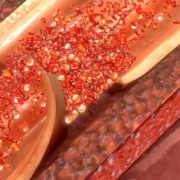

O desenvolvimento de aterosclerose representa a maior causa dos aneurismas, tratando-se do envelhecimento arterial seguido de deposição de placas de gordura (ateromas) nos vasos.

A aterosclerose pode obstruir ou dilatar vasos. Quando ocorre aneurisma, acontece um consequente enfraquecimento da parede da artéria afetada, que culmina com posterior dilatação da região.

O desenvolvimento da aterosclerose tende a ser lento, de maneira que tem a capacidade de acometer outras artérias. Alguns fatores de riscos são os seguintes:

Pelo fato de apresentarem coágulos sanguíneos em seu interior, os aneurismas podem ocasionar isquemias, reduzindo a circulação sanguínea.

As isquemias podem ocorrer no cérebro, quando da ruptura de aneurismas na aorta torácica, bem como nos membros inferiores, se a ocorrência se der na aorta abdominal ou torácica. Neste último caso, tal complicação tende a ocorrer de forma mais rara.